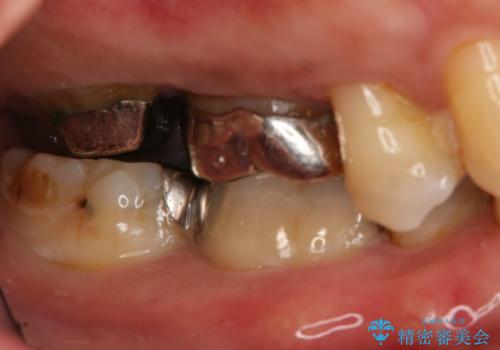

- 右上大臼歯の被せ物が取れたので作り直しを希望された患者様です。

被せ物は白くしたいとのことだったのでフルジルコニアクラウンでの治療を選択しました。

根管治療も必要だったので金属の土台を除去し、新しく土台を立て直した上で被せ物を装着しています。